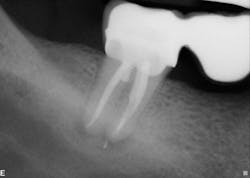

The first case involves a 49-year-old female. Tooth no. 31 had a deep periodontal probing on the straight buccal. The patient was warned that the tooth might be fractured, but she still decided on treatment (figure 1).

Calcium hydroxide paste medication was placed in the canals on three visits, each two weeks apart. Treatment included a total of six weeks of calcium hydroxide therapy.